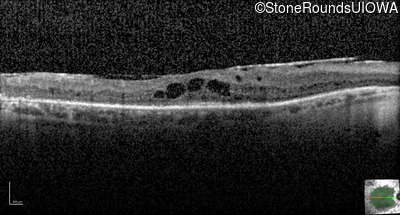

Optical Coherence Tomography - Right - 20/63

Exemplar / OCT Stack